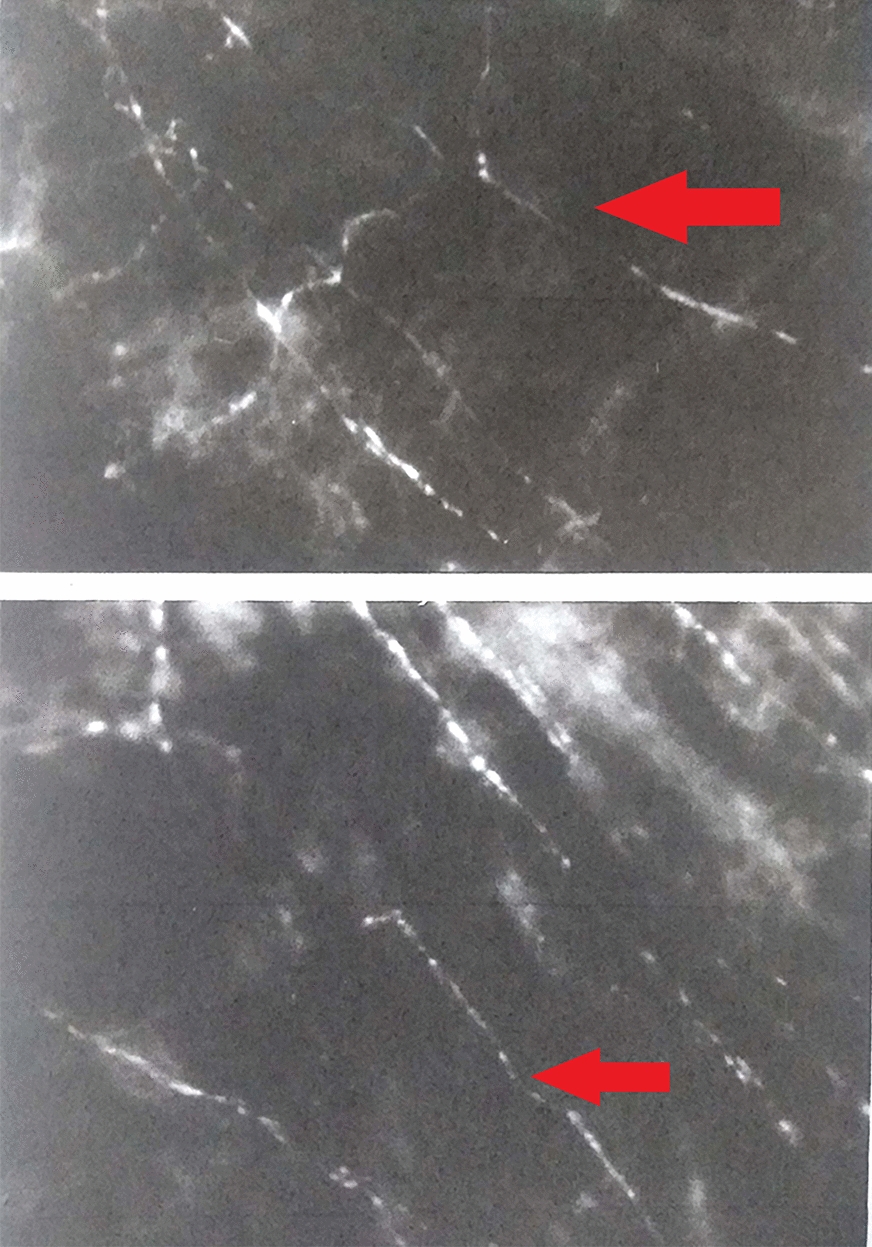

Fig. 5.

“en face” OCT analysis of Haller layer (OS, image on the left) and Sattler layer in a myopic patient (OD, image on the right). Sattler layer was not detectable in patients with regular fundus due to reflective properties of healthy EPR. Large vessels are represented by hyporeflective areas in the surrounding stroma (blue arrow)

OCT angiography

The same layers have been studied with OCT angiographic method, with “en face” scans. The anatomical structure of the choriocapillary is not clearly displayed, but the resulting image is characterized by a granular appearance of light and dark areas of different sizes and the individual capillaries are not clearly visible (Fig. 6). The flow in the deeper layers of the choroid cannot be visualized at OCT A, due to the reflective properties of the retinal pigment epithelium, and appeared as darker areas corresponding the vascularization of the Sattler and Haller layers (Fig. 7).

Fig. 6.

Choriocapillaris in OCT (image on the left) and OCT-A “en face” analysis (image on the right)

Fig. 7.

Sattler (image on the left) and Hattler (image on the right) layers in a myopic patient visualized in OCT-A “en face” analysis. Choroidal vessels are visualized as hyporeflective areas (blue arrow)